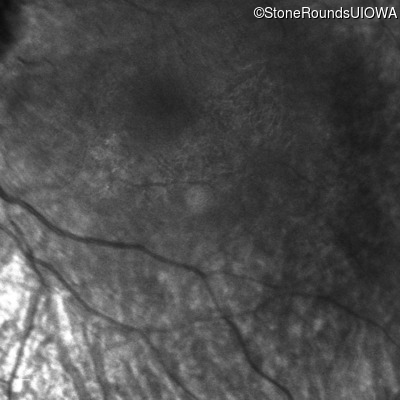

Infrared Fundus Photograph - Right -

No Light Perception

Infrared Fundus Photograph - Left -